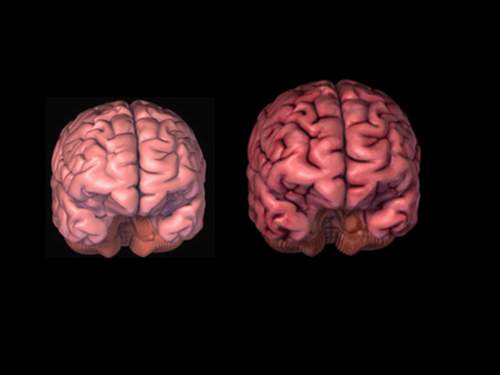

إذا قمنا بوزن دماغ رجل ودماغ امرأة سنجد أن دماغ الرجل أثقل بنسبة لا تقل عن 10 بالمئة وقد تصل إلى 20 بالمئة أحياناً، وهذا اختلاف يُضاف للاختلافات الكثيرة بين الرجل والمرأة. وحتى نسبة موت الخلايا في الدماغ تختلف من الرجل إلى المرأة، وطريقة عمل هذه الخلايا تختلف، فقد وجد الباحثون أن نسبة انكماش الدماغ (تنكس الخلايا) عند الرجل أكبر منه وأكثر وضوحاً من المرأة مع تقدم العمر. وهكذا اختلاف في كل شيء تقريباً..

بينت الدراسات أن حجم دماغ الرجل أكبر من حجم دماغ المرأة عند نفس العمر، وذلك بعشرة إلى عشرين بالمئة، وهذه الزيادة عند الرجل في حجم دماغه تجعله مختلفاً عن المرأة في الكثير من العمليات الدماغية.